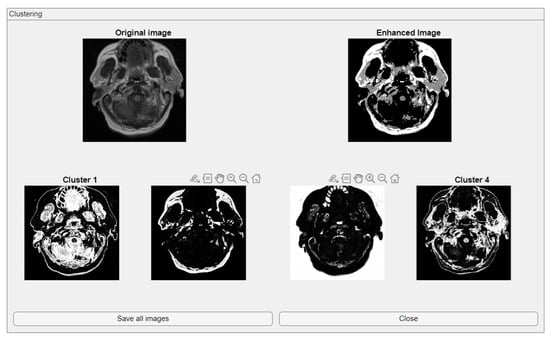

2.2. Clustering

The Clustering module integrates fuzzy C-means (FCM) clustering for unsupervised image segmentation [37]. This functionality supports the automatic classification of image regions based on pixel intensity distributions while accommodating partial membership, which is particularly suitable for medical images where tissue boundaries may not be well defined. The module also provides the option to save both the clustered image and the enhanced image, enabling users to store intermediate and final processing results for future reference or external evaluation. This added functionality ensures that the outputs of the clustering process can be efficiently archived or used in subsequent processing steps.

The comparative charts and visual presentation of edges allow for a detailed analysis of each algorithm’s strengths and weaknesses, offering insight into the trade-offs between edge completeness and false detection rates. Figure 4 illustrates the fuzzy C-means (FCM) clustering results obtained from the four case studies: CS1, CS2, DU1, and DU2. Each subfigure (A, B, C, and D) presents the following sequence:

-

Original Image: The initial input image from the dataset.

Enhanced Image: The result after applying image enhancement techniques to improve contrast and feature visibility, likely to support better clustering outcomes.

Clusters 1 to 4: The segmentation outputs, where the image has been partitioned into four distinct clusters. Each cluster highlights different regions based on pixel similarity, potentially corresponding to anatomical structures, tissues, or specific features of interest within the medical images.

Key Observation: Figure 4 and Figure A1 collectively showcase the clustering module’s capacity to aid in visual discrimination and structural interpretation across the studied medical cases.

Figure 4. Clustering with fuzzy C-means (FCM) results within iMIA platform: The clusters emphasize various structural and textural components, with some clusters isolating specific regions with clear edges and others focusing on more homogeneous areas. The segmentation reveals critical areas with varying intensity patterns, possibly indicative of different tissue types or pathological regions: TCGA_CS_4941_19960909_3 (CS1) (additional results are shown in Figure A1).

Figure A1. Clustering with fuzzy C-means (FCM) results within iMIA platform. (b) TCGA_CS_4941_19960909_14 (CS2), (c) TCGA_DU_5872_19950223_1 (DU1), (d) TCGA_DU_5872_ 19950223_35 (DU2) (refer to the image (a) CS1 result in Figure 4).